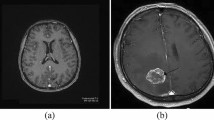

Investigation of brain cancer can detect the abnormal growth of tissue in the brain using computed tomography (CT) scans and magnetic resonance (MR) images of patients. The proposed method classifies brain cancer on shape-based feature extraction as either benign or malignant. The authors used input variables such as shape distance (SD) and shape similarity measure (SSM) in fuzzy tools, and used fuzzy rules to evaluate the risk status as an output variable. We presented a classifier neural network system (NNS), namely Levenberg–Marquardt (LM), which is a feed-forward back-propagation learning algorithm used to train the NN for the status of brain cancer, if any, and which achieved satisfactory performance with 100% accuracy.

The proposed methodology is divided into three phases. First, we find the region of interest (ROI) in the brain to detect the tumors using CT and MR images. Second, we extract the shape-based features, like SD and SSM, and grade the brain tumors as benign or malignant with the concept of SD function and SSM as shape-based parameters. Third, we classify the brain cancers using neuro-fuzzy tools. In this experiment, we used a 16-sample database with SSM (μ) values and classified the benignancy or malignancy of the brain tumor lesions using the neuro-fuzzy system (NFS).

We have developed a fuzzy expert system (FES) and NFS for early detection of brain cancer from CT and MR images. In this experiment, shape-based features, such as SD and SSM, were extracted from the ROI of brain tumor lesions. These shape-based features were considered as input variables and, using fuzzy rules, we were able to evaluate brain cancer risk values for each case. We used an NNS with LM, a feed-forward back-propagation learning algorithm, as a classifier for the diagnosis of brain cancer and achieved satisfactory performance with 100% accuracy. The proposed network was trained with MR image datasets of 16 cases. The 16 cases were fed to the ANN with 2 input neurons, one hidden layer of 10 neurons and 2 output neurons. Of the 16-sample database, 10 datasets for training, 3 datasets for validation, and 3 datasets for testing were used in the ANN classification system. From the SSM (µ) confusion matrix, the number of output datasets of true positive, false positive, true negative and false negative was 6, 0, 10, and 0, respectively. The sensitivity, specificity and accuracy were each equal to 100%.